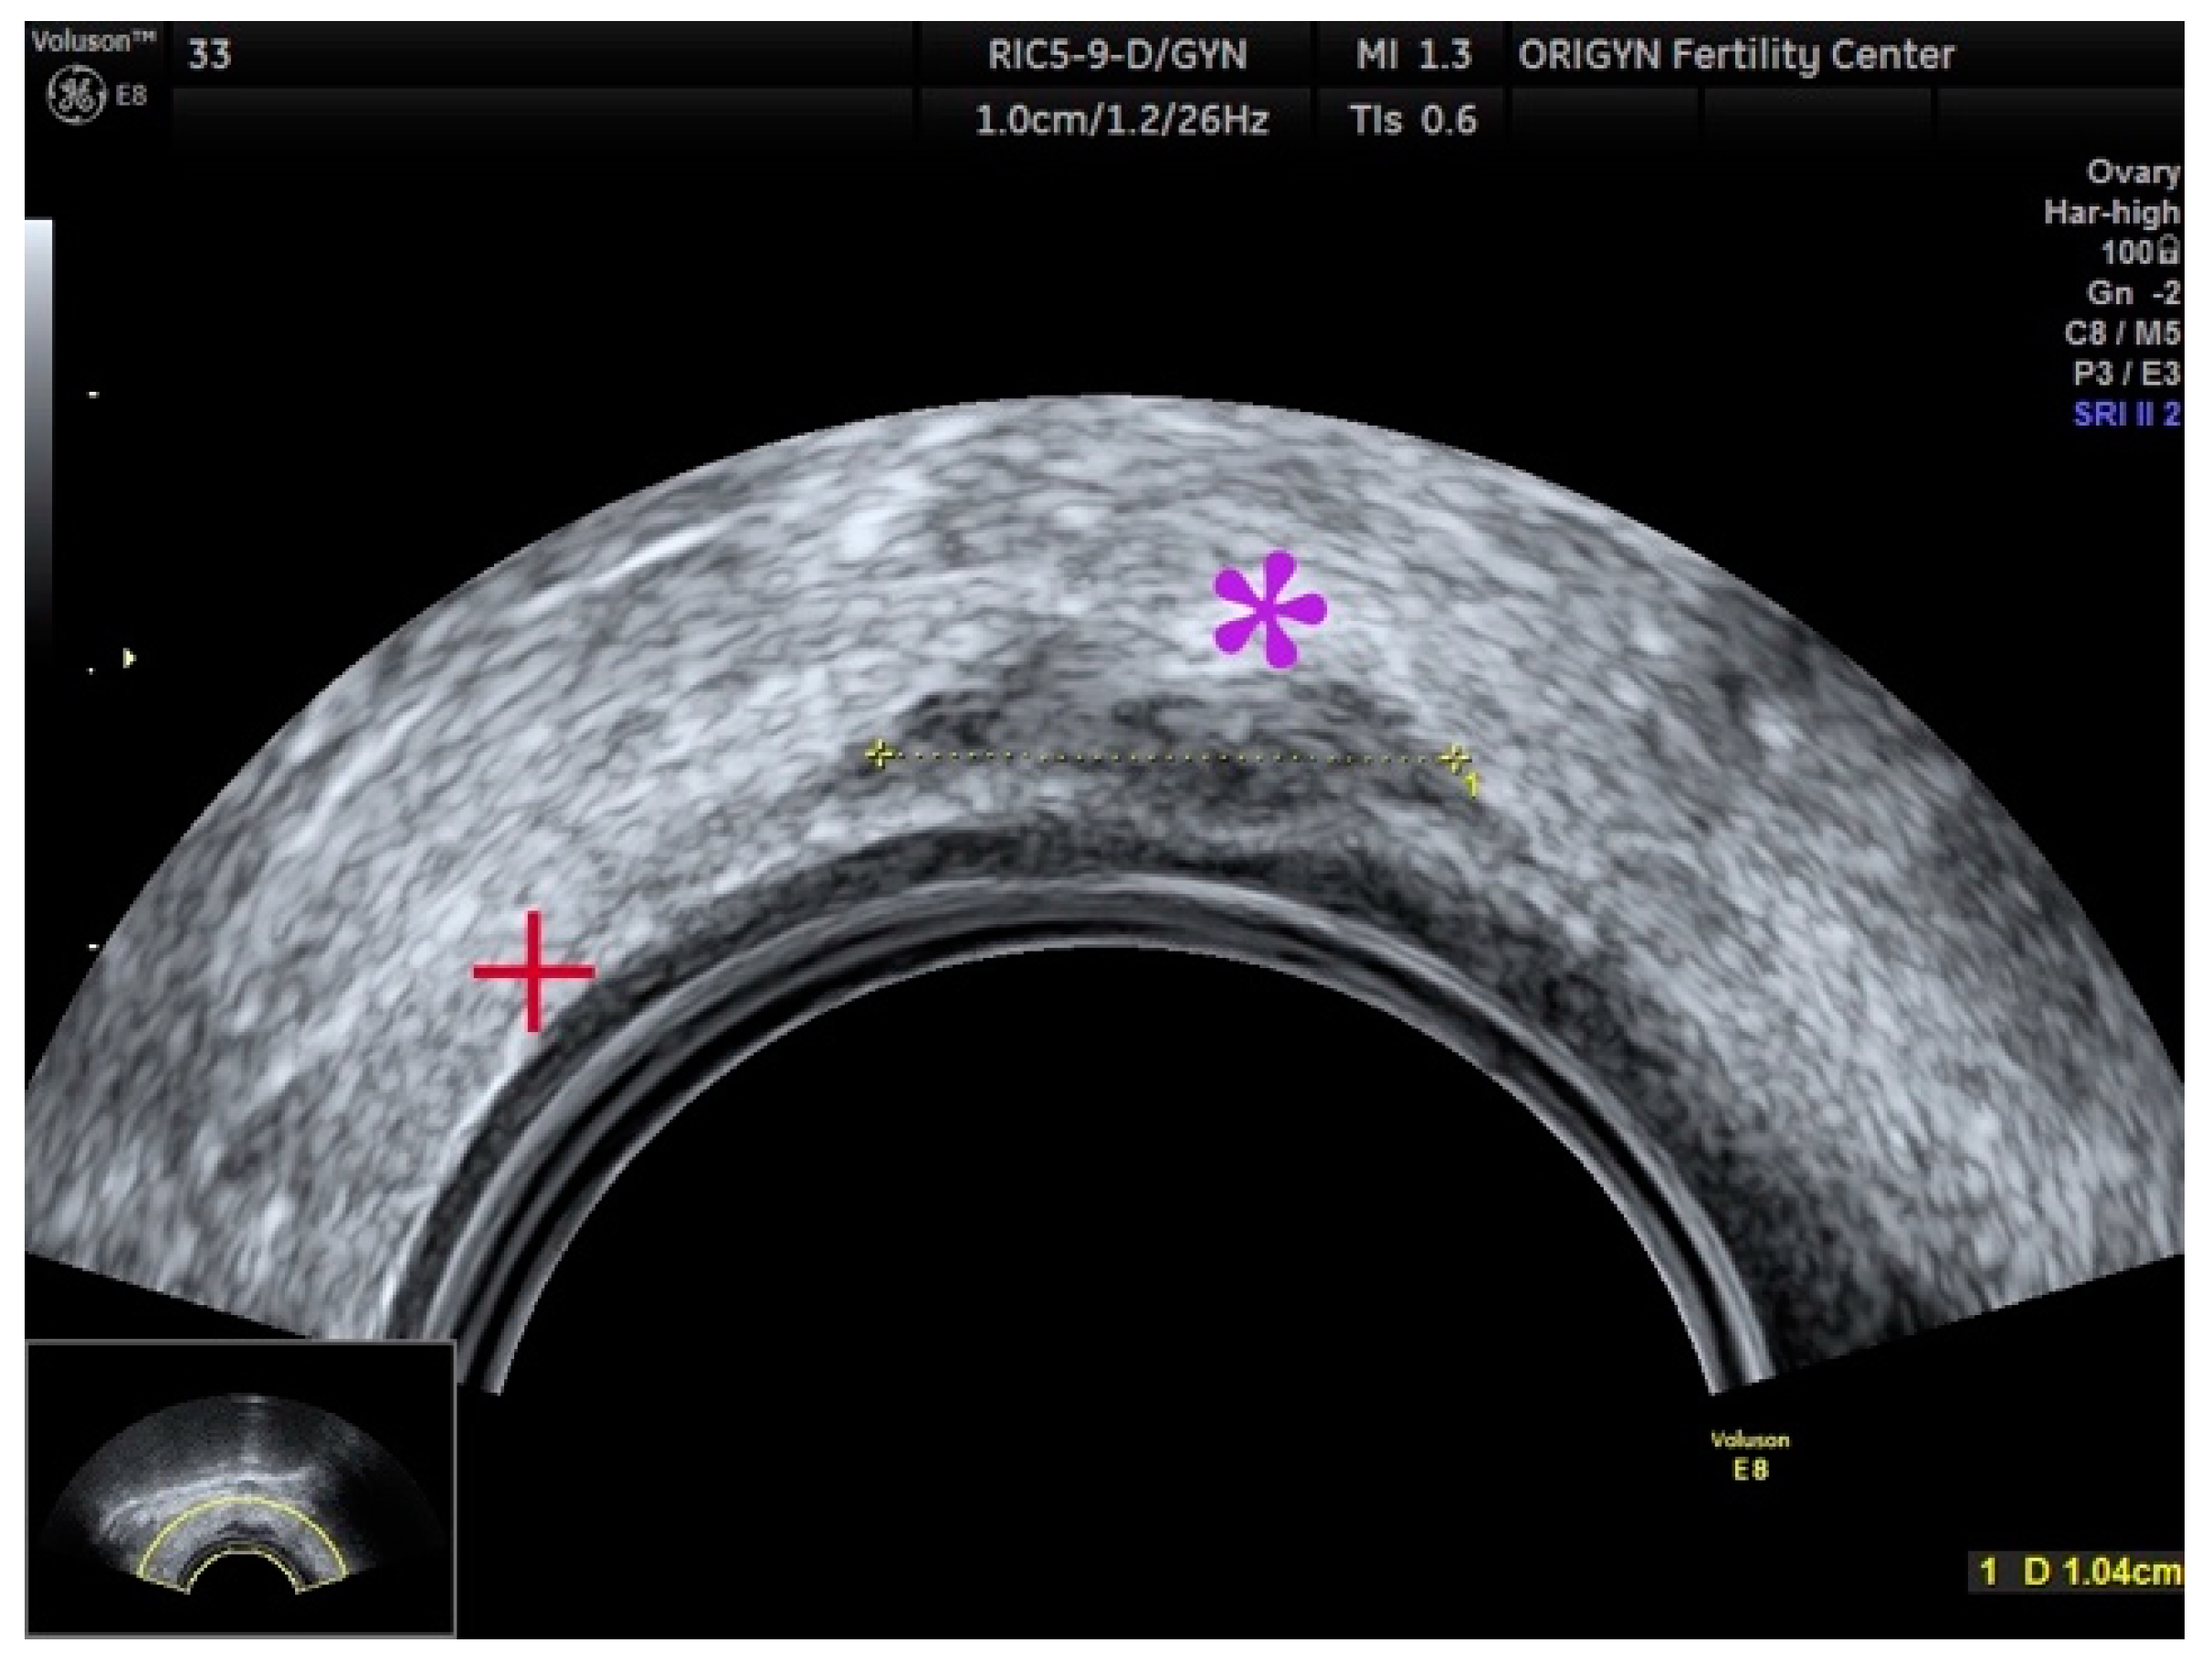

3.1. ADNEXA